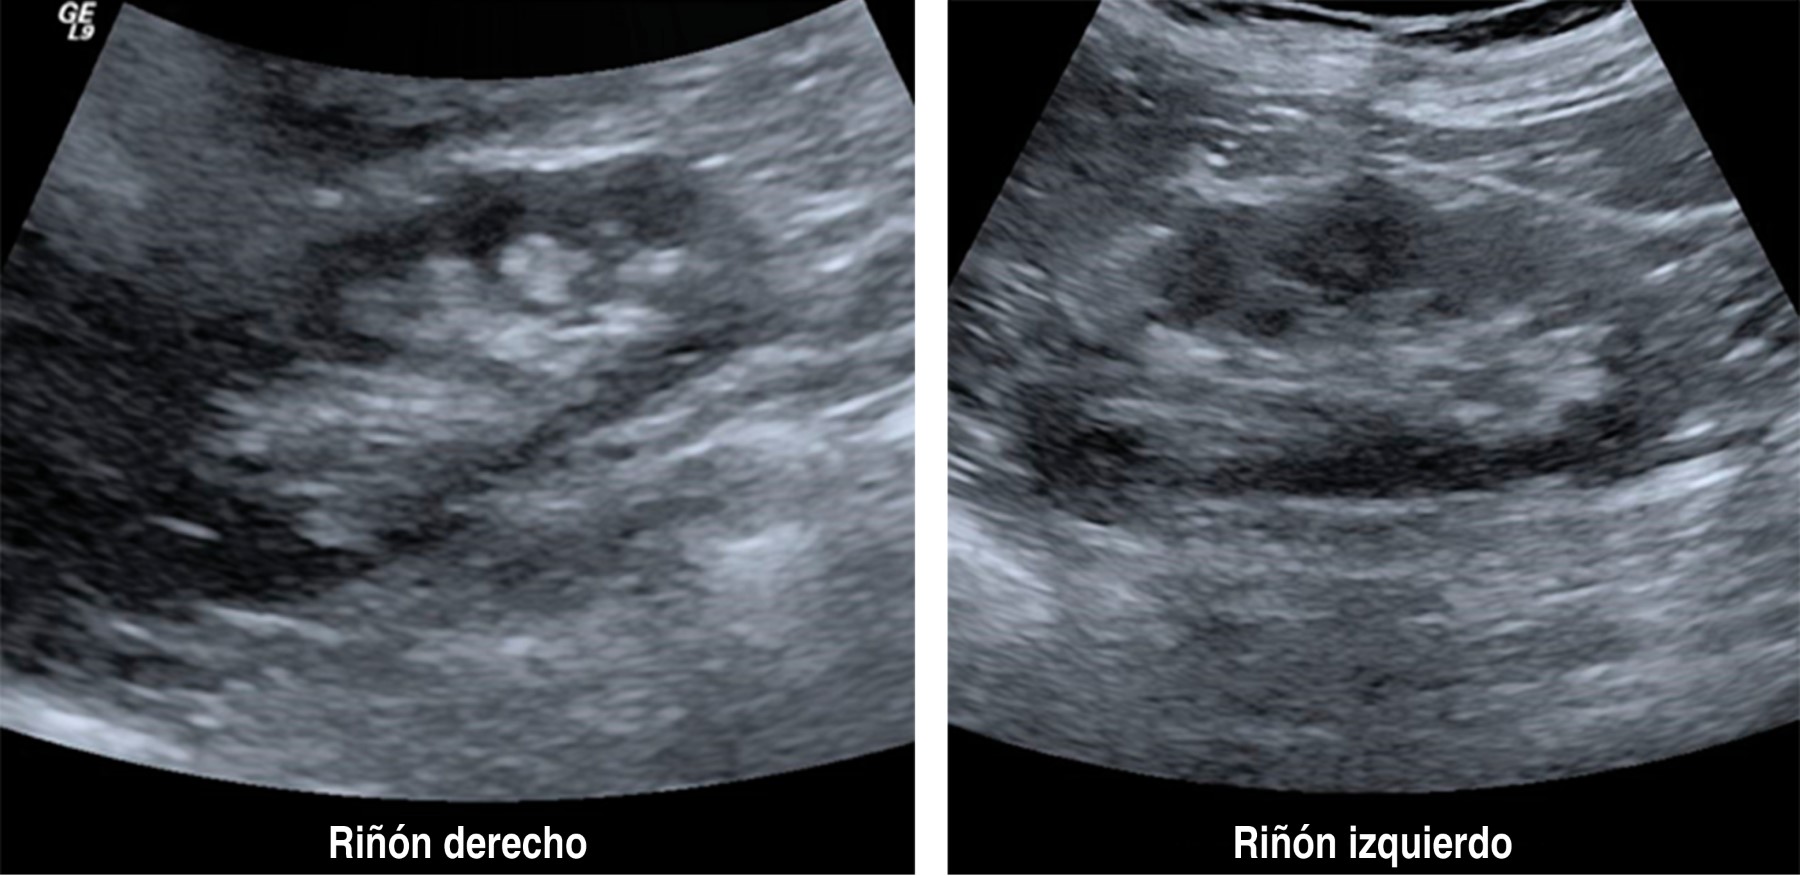

En el ultrasonido renal se observan ambos riñones de tamaño normal, con pérdida de la relación córtico-medular, con pirámides francamente ecogénicas en relación a nefrocalcinosis bilateral, sin evidencia de dilatación de los sistemas colectores (Figura 3).

Ultrasonido renal muestra en riñón izquierdo dilatación pielocalicial con imágenes ecogénicas en pirámides sugestivas de nefrocalcinosis (Figura 8).

El caso 1 inicialmente tuvo insuficiencia renal aguda, que remitió sin terapia de reemplazo renal, ya que no tuvo criterios para diálisis. Además, se comprobó hipercalciuria hipercalcémica y supresión de la hormona paratiroidea como ocurrió en el caso 1 y el 2 acompañada de disminución de la reabsorción tubular de fosfatos, que condicionó nefrocalcinosis (Figuras 3 y 8).